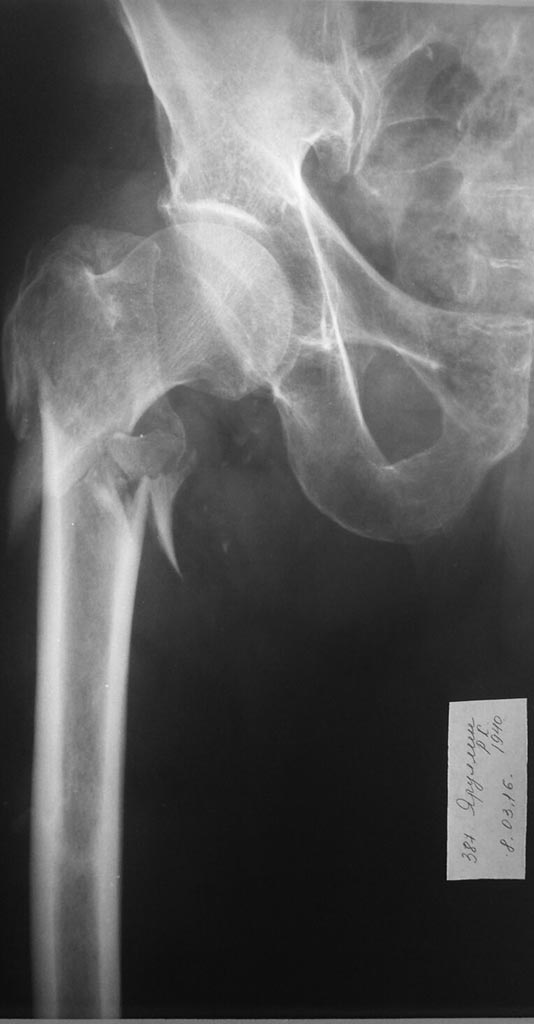

до

Хотелось бы посмотреть на свежий снимок оперированного отдела бедра. Может, там все развалилось уже, и это и есть причина лихорадки?